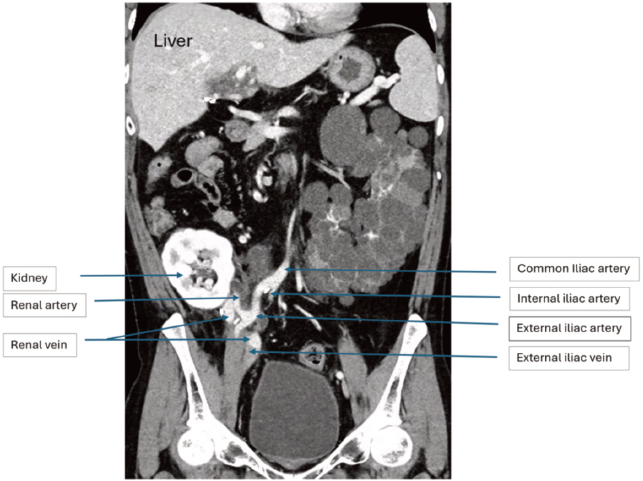

We proceeded with right-side nephrectomy im-mediately after completion of the liver transplant. The kidney hilum was exposed, and the renal artery and renal vein were secured and divided. The ureter was divided at the level of iliac vessels with careful preservation of the blood supply to the distal ureter.The kidney graft was transplanted into the right iliac fossa using the same incision. We used a right medial visceral rotation (the Cattell-Braasch maneuver) to gain access to the iliac vessels. The renal artery and renal vein were anastomosed to the external iliac artery (EIA) and the external iliac vein (EIV), respectively, using 5/0 polypropylene nonabsorbable monofilament (Prolene) sutures (Figure 2). The total cold ischemia time was 13 hours, and warm ischemia time was 38 minutes.

Here, we have described a case in which the same reverse L incision of the liver transplant was emp-loyed for a right-side native nephrectomy and kidney transplant. The exposure by this approach for the EIA and EIV were appropriate for kidney graft imp-lantation. The kidney graft ureter was anastomosed to the remaining native ureter in an end-to-end fashion (ureteroureterostomy). There was no urine leak or ureter stenosis during 12 months of follow-up. This approach is therefore feasible and effective for SLKT.